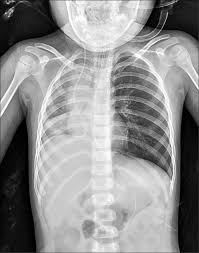

圖片來源:《自由時報》,示意圖。

深夜轉入加護病房後,醫師決定使用軟式支氣管鏡深入檢查,真相這才揭曉——原來有一顆花生卡在氣管裡,隨著呼吸節奏上下劇烈晃動,阻塞超過七成的氣道,形成致命的「球閥效應」,空氣能進卻無法順利排出,臨床上稱為「跳舞花生」。即便完成插管,花生仍持續移動,男童呼吸速率飆到每分鐘49次,低血氧問題始終無法改善。隔天清晨,花生滑進右主支氣管,導致右肺完全塌陷、縱膈腔偏移,情況更加惡化。醫療團隊緊急推進手術室,改用專門移除異物的硬式支氣管鏡處理,耳鼻喉科醫師順利取出這顆折磨孩子將近24小時的花生,術後血氧終於穩定回升至99%。